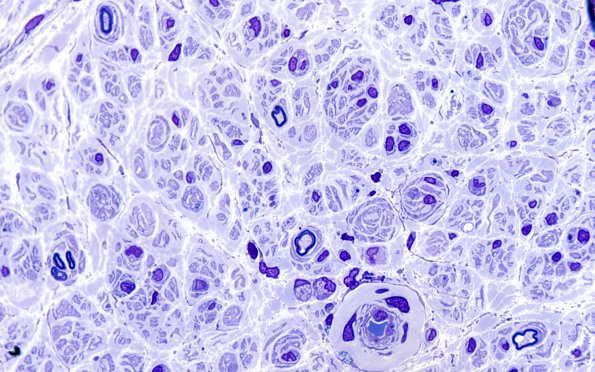

Washington University Experience | PERIPHERAL NEUROPATHY | 7A GUILLAIN-BARRE SYNDROME (GBS) | 10A1 (Case 10) 100X sp GBS. 1

Case 10 History ---- The patient is a 45 year old woman with muscle weakness. ---- 10A1,2 A few relatively large axons without myelin sheaths are noted which are intimately associated with macrophages carrying myelin debris consistent with an active, macrophage mediated demyelination. There is a hint of onion bulb or pseudo-onion bulb formation, suggesting the possibility of CIDP.